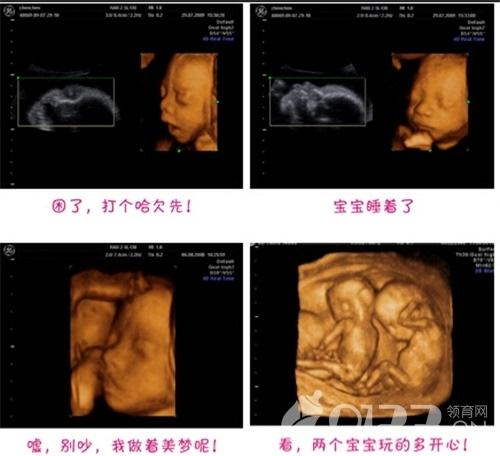

接下来我们一起去看看彩超筛查过程,胎宝宝一些神奇而调皮的举动: 打